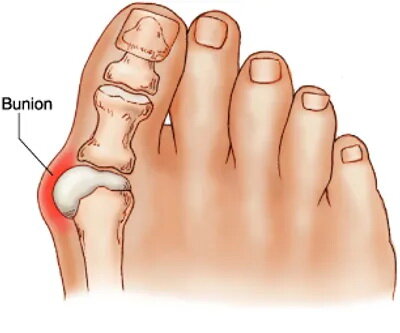

علت انحراف شست پا چیست؟ ۱۴.۷ | مطالب پیشنهادی (مشابه) | ذخیره شده

۲۷ تیر ۱۳۹۸ — علت انحراف شست پا چیست؟

علت انحراف شست پا چیست؟ ۱۴.۷ | مطالب پیشنهادی (مشابه) | ذخیره شده

۲۷ تیر ۱۳۹۸ — علت انحراف شست پا چیست؟